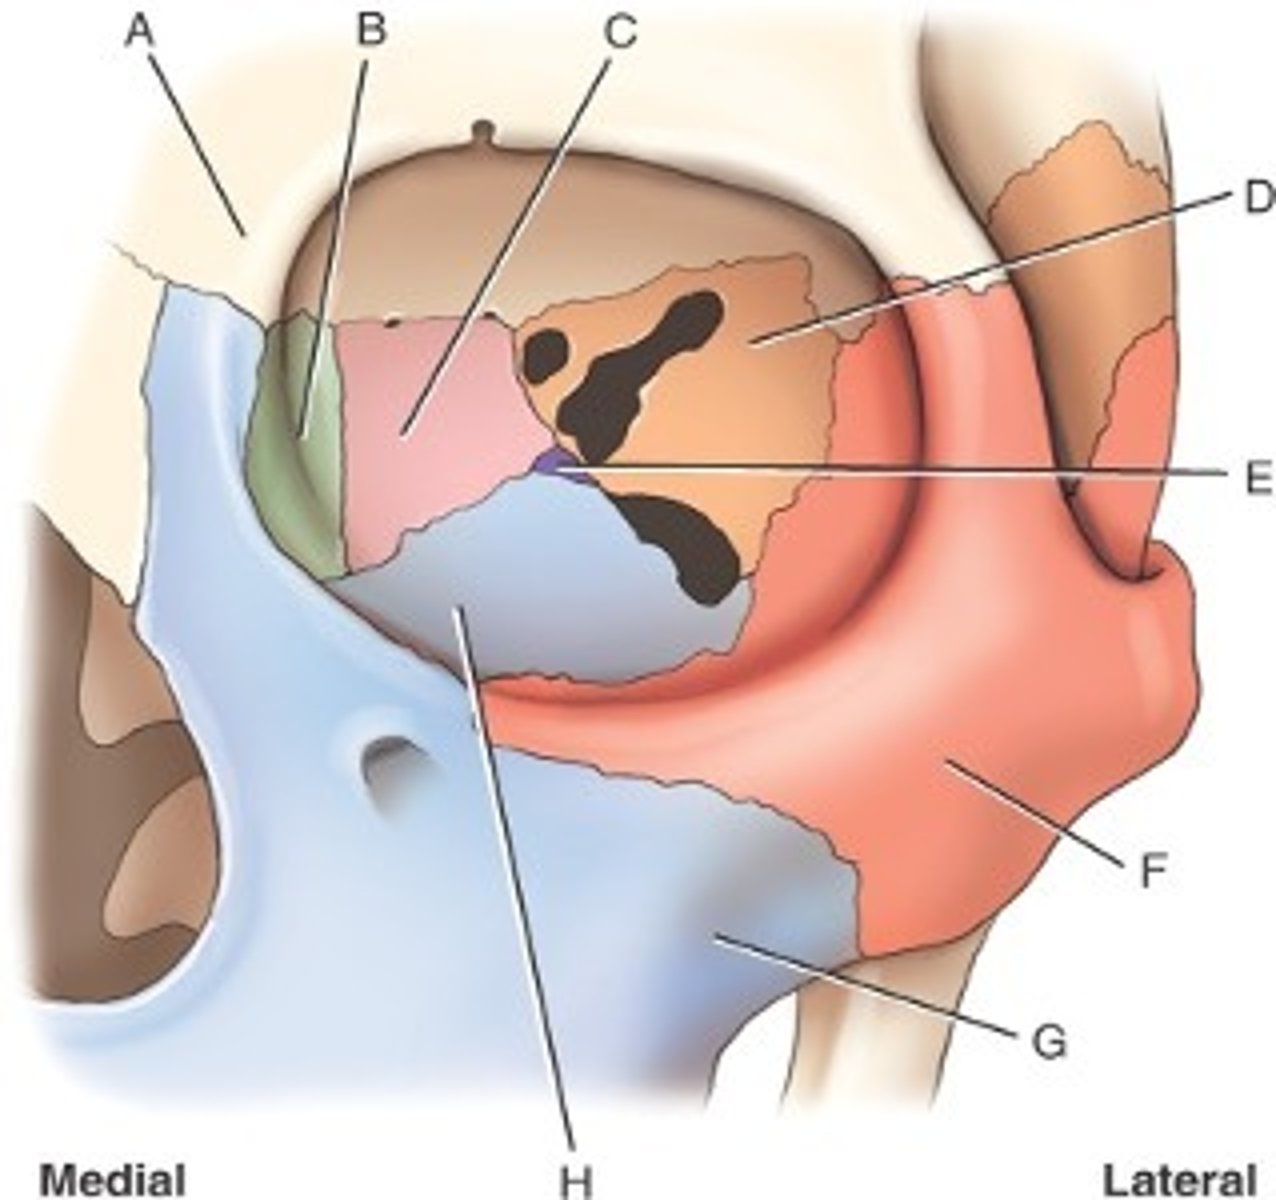

What is B

frontal bone

What is A

ethmoid

What is C

sphenoid

what is D

Palatine

What is E

Zygoma

What is F

Maxilla

What is G and H

optic foramen in orbit

sphenoid strut